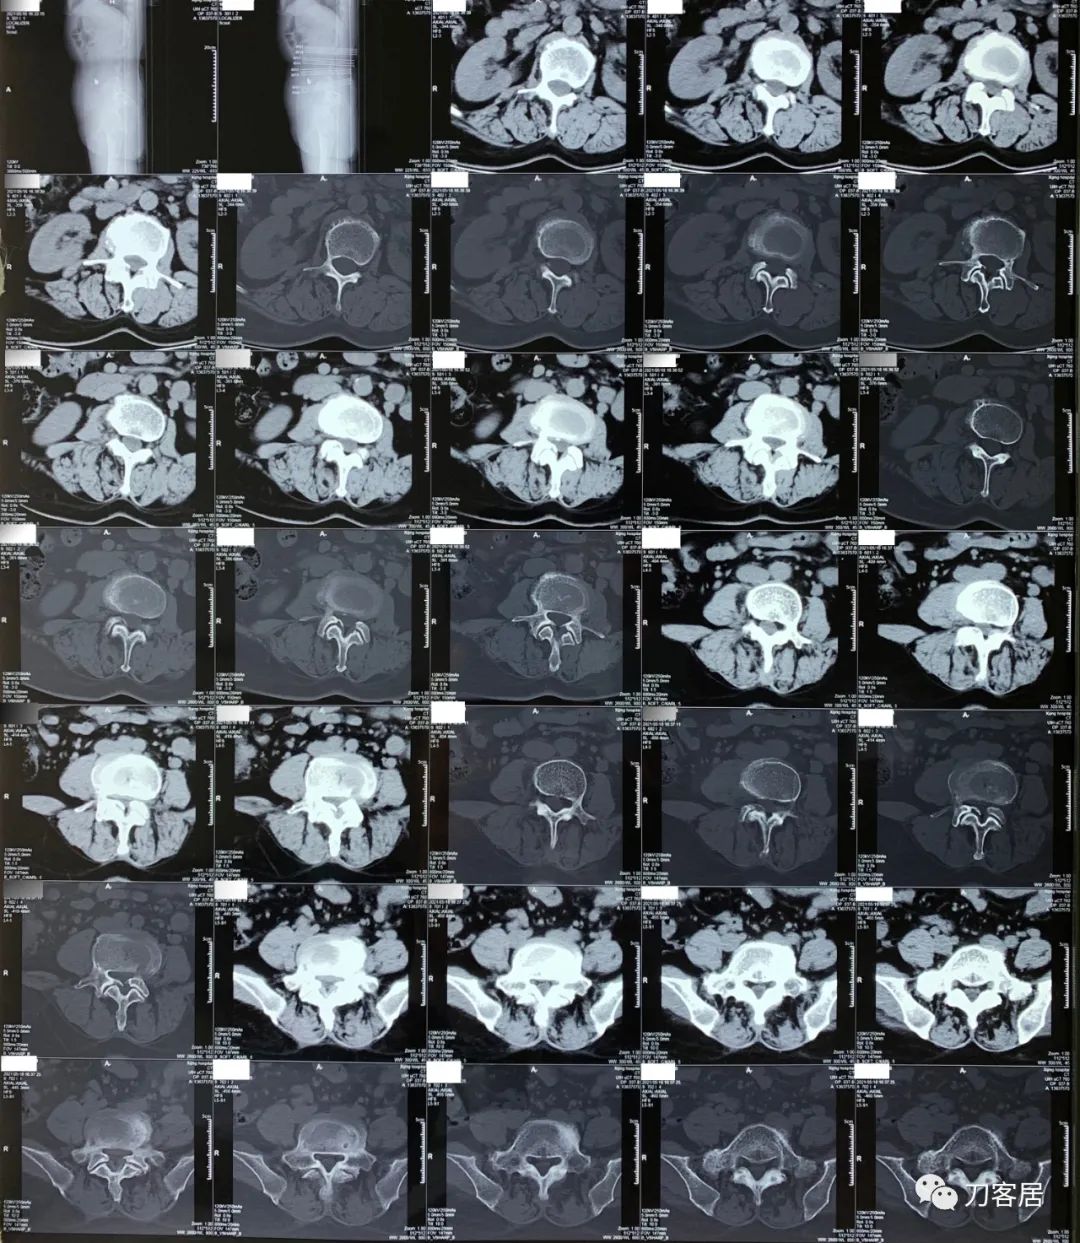

建议其查双光子骨密度,骨盆正位片以及腰椎间盘平扫。腰椎正侧位X线片以及动力位片,站立位脊柱全长正侧位X线片,以了解其是否有骨质疏松,并了解脊柱侧弯情况,腰椎局部X线表现情况和腰椎间盘突出和椎管狭窄情况。

从这个患者的影像资料分析,颈椎间盘突出问题不大,没有明确的上位神经元损伤表现,所以,不考虑颈椎和胸椎问题。腰椎侧弯畸形,但不严重。因为存在腰椎侧弯,使得腰椎MRI在扫描切面的时候,显示的椎间盘突出或椎管狭窄会有一定的误差,所以,又加做了经椎间盘的CT平扫,影像表现并不严重,综上,腰椎间盘突出,腰椎管狭窄,腰椎侧弯,不考虑手术治疗。同时,患者的主要痛苦是心理疾病,而不是器质性疾病,所以,以心身疾病治疗为主。虽然患者骨密度检查结果提示正常,但X线片显示骨质疏松,且其症状也与骨质疏松的症状有符合之处,比如静息痛,不能入睡,动作及姿势变换时痛加重等,所以,给予实验性抗骨质疏松治疗,以观疗效。